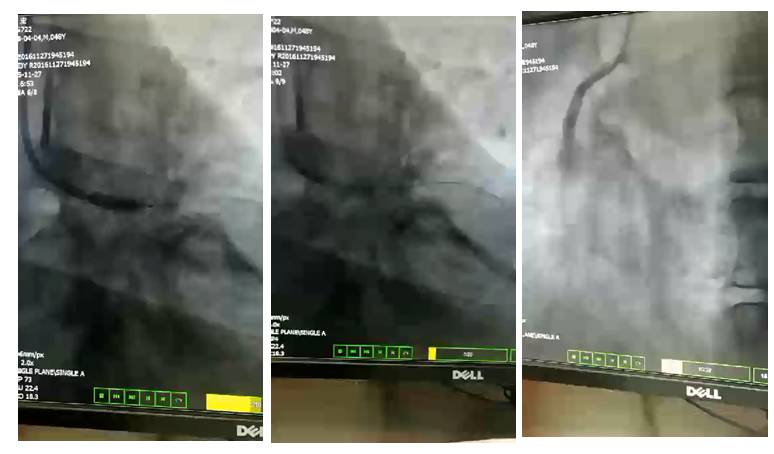

22:15 清醒状态下VA-ECMO术

◆22:21 血压回升至102/56mmHg,氧饱和度100%,可见清亮尿液。

◆23:30 左下肢感觉障碍,皮温降低、花斑、足背动脉搏动未触及;

23:55 ECMO下肢分流术

保证下肢供血